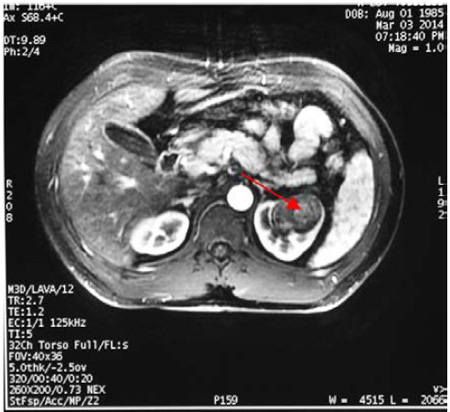

10、双肾磁共振平扫

+增强

、醛固酮;影像学提示左肾占位性病变;肾血管未见异常;

提示高肾素、高醛固酮,查双肾超声及双肾MRI提示右肾上极存在占位,临床诊断主要考虑肾素瘤。临床上需要鉴别肾性或肾血管性高血压,肾血管性高血压一般表现为中重型血压升高,一般对降压药物效果不佳,有时呈急进性或恶性高血压,上腹部脐周和腰背部有时常可闻及收缩期或连续性血管杂音

4、B 超和CT是最常用的影像检查手段。B超检查病变可表现为肾皮质内低或中强各种回声。本次报告的第二例患者可能由于存在瘤体内的出血而显示不均质回声。CT平扫+动态增强扫描是有效的定位诊断方法,敏感性接近100%。CT平扫常表现稍低至等密度,增强后在动脉期常与肾实质其他部位一致,但在门脉期或延迟期可有轻-中度强化而与周期肾实质存在差异。